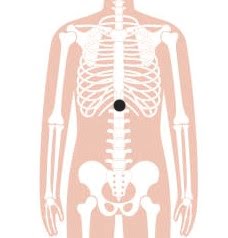

3. Zhongwan

Zhongwan, ofwel Centrale Venter 12 (CV12), is een ander belangrijk acupunctuurpunt voor gewichtsverlies en ligt iets boven de navel. Dit acupunctuurpunt heeft ook een direct effect op de organen van de bovenbuik, evenals op de organen die betrokken zijn bij de spijsvertering, zoals de maag en darmen. Dit acupunctuurpunt kan de bloedsuikerspiegel helpen te verlagen. Hierdoor kan het de oorsprong en progressie van aan obesitas gerelateerde aandoeningen zoals diabetes mellitus type 2 voorkomen en het individu helpen gewicht te verliezen.